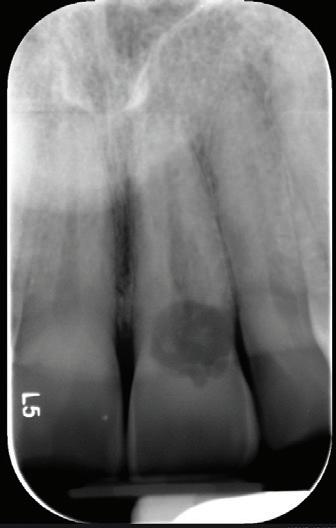

RECONFIGURAREA suportului osos implantar. În cazul prezentat, după ani de terapie ortodontică incorect executată, dezvoltarea dentară a pacientului a complicat obținerea unui zâmbet estetic. S-a reanalizat și s-a optat pentru abordare interdisciplinară care cuprinde chirurgia parodontală, un al doilea tratament

ortodontic și protetica pentru a oferi îngrijirea comprehensivă.